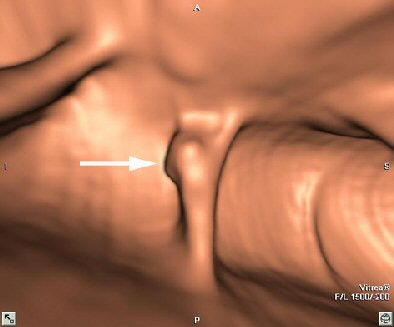

| Endoluminal VC image demonstrates relationship of the polyp (arrow) with colonic haustral fold. Image courtesy of Dr. Riccardo Iannaccone. |

An audience member asked how unprepped colons could end up looking so clean -- at least in the examples shown in the presentation. Iannaccone said the combination of a low-residue diet and mild prep caused by the oral contrast agent produces relatively clean images in some patients.

"Gastrografin has a mild cathartic effect -- a well-known and wanted side effect that produces diarrhea, although it is certainly not ... comparable with standard cathartic preps," he said. "However, in the majority of patients, fecal material was actually present and homogeneously tagged."